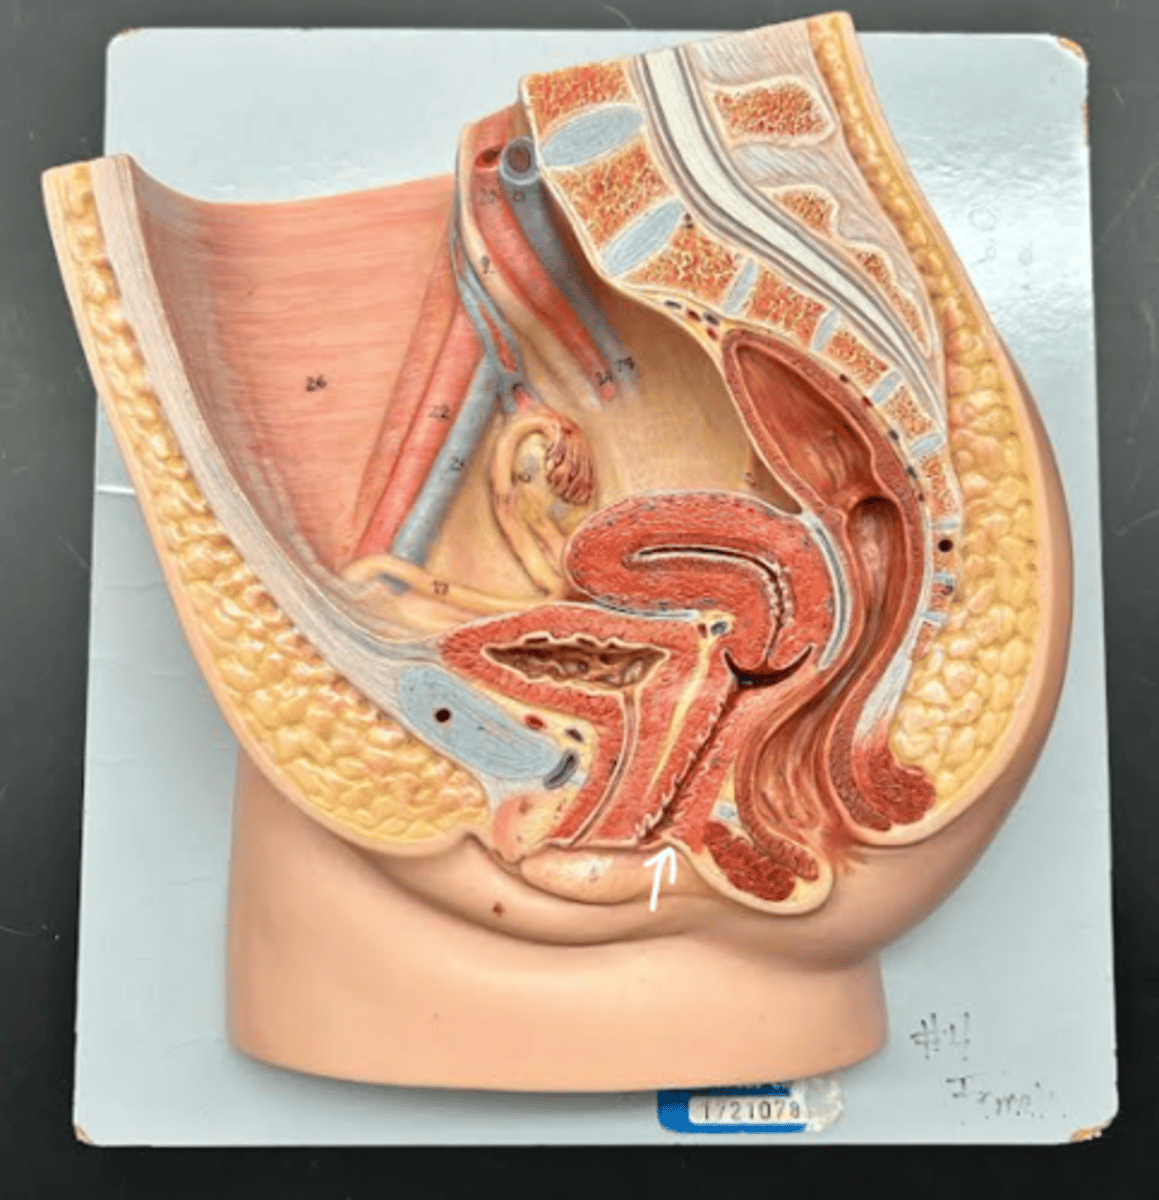

Chapter 29 Anat Phys: Female Reproductive System

Vagina

Vaginal orifice

Hymen

Vaginal fornix

Ovary

Fallopian tube

Fimbriae

Infundibulum

Ampulla

Isthmus

Uterus

Perimetrium

Myometrium

Endometrium

Fundus

Body of uterus

Cervix

Internal os

Cervical canal

External os

Labia majora

Labia minora

Prepuce

Vestibule

Clitoris

External urethral orifice